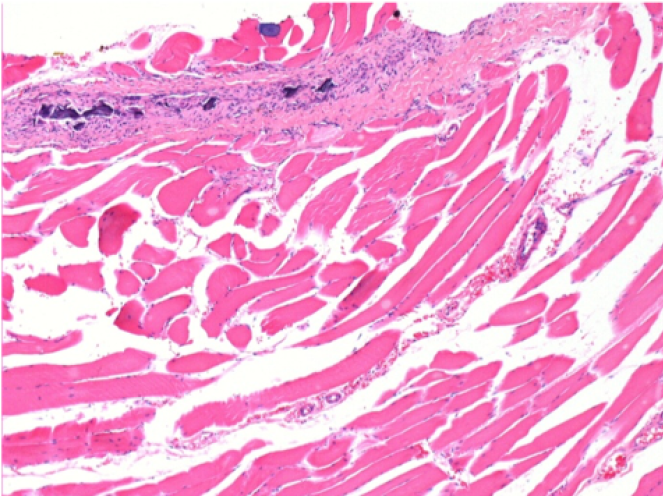

3 months (D90)after Endopeel Injection 0.1ml in the right pretibial muscle.

7 months (D210)after Endopeel IM Injection 0.1ml in the right pretibial muscle.

Complete Restitutio ad integrum after 7 months